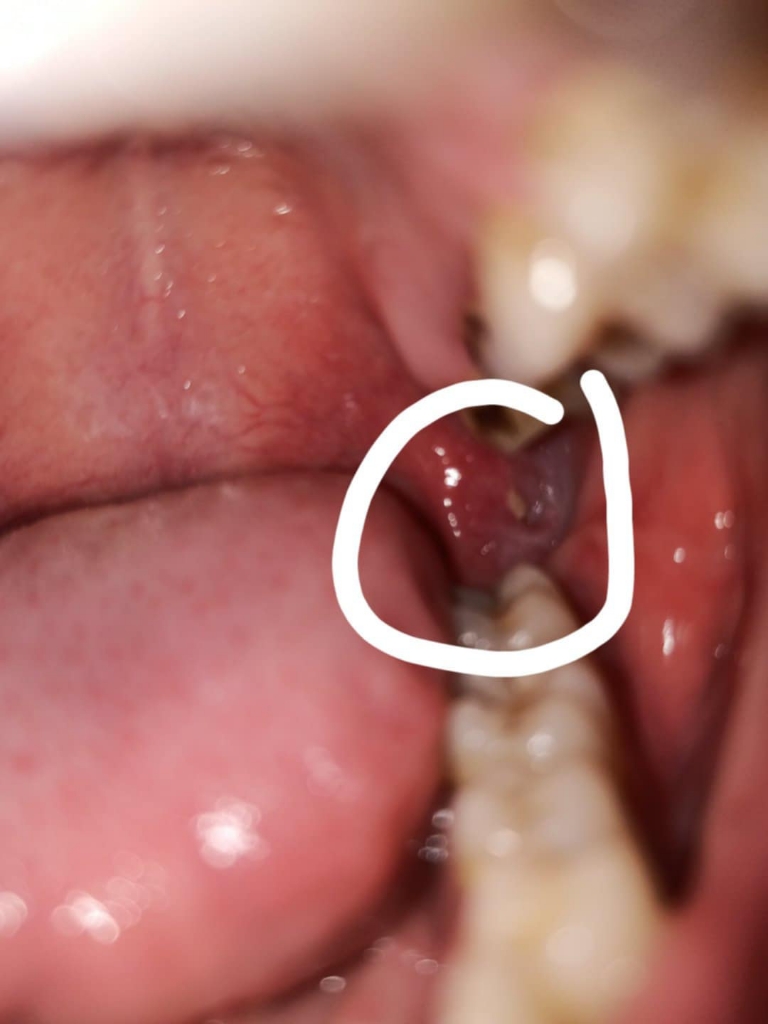

Bác sĩ cho hỏi đây là nhiệt miệng hay là mọc răng khôn ạ , mình nhức cả tuần rồi ko giảm